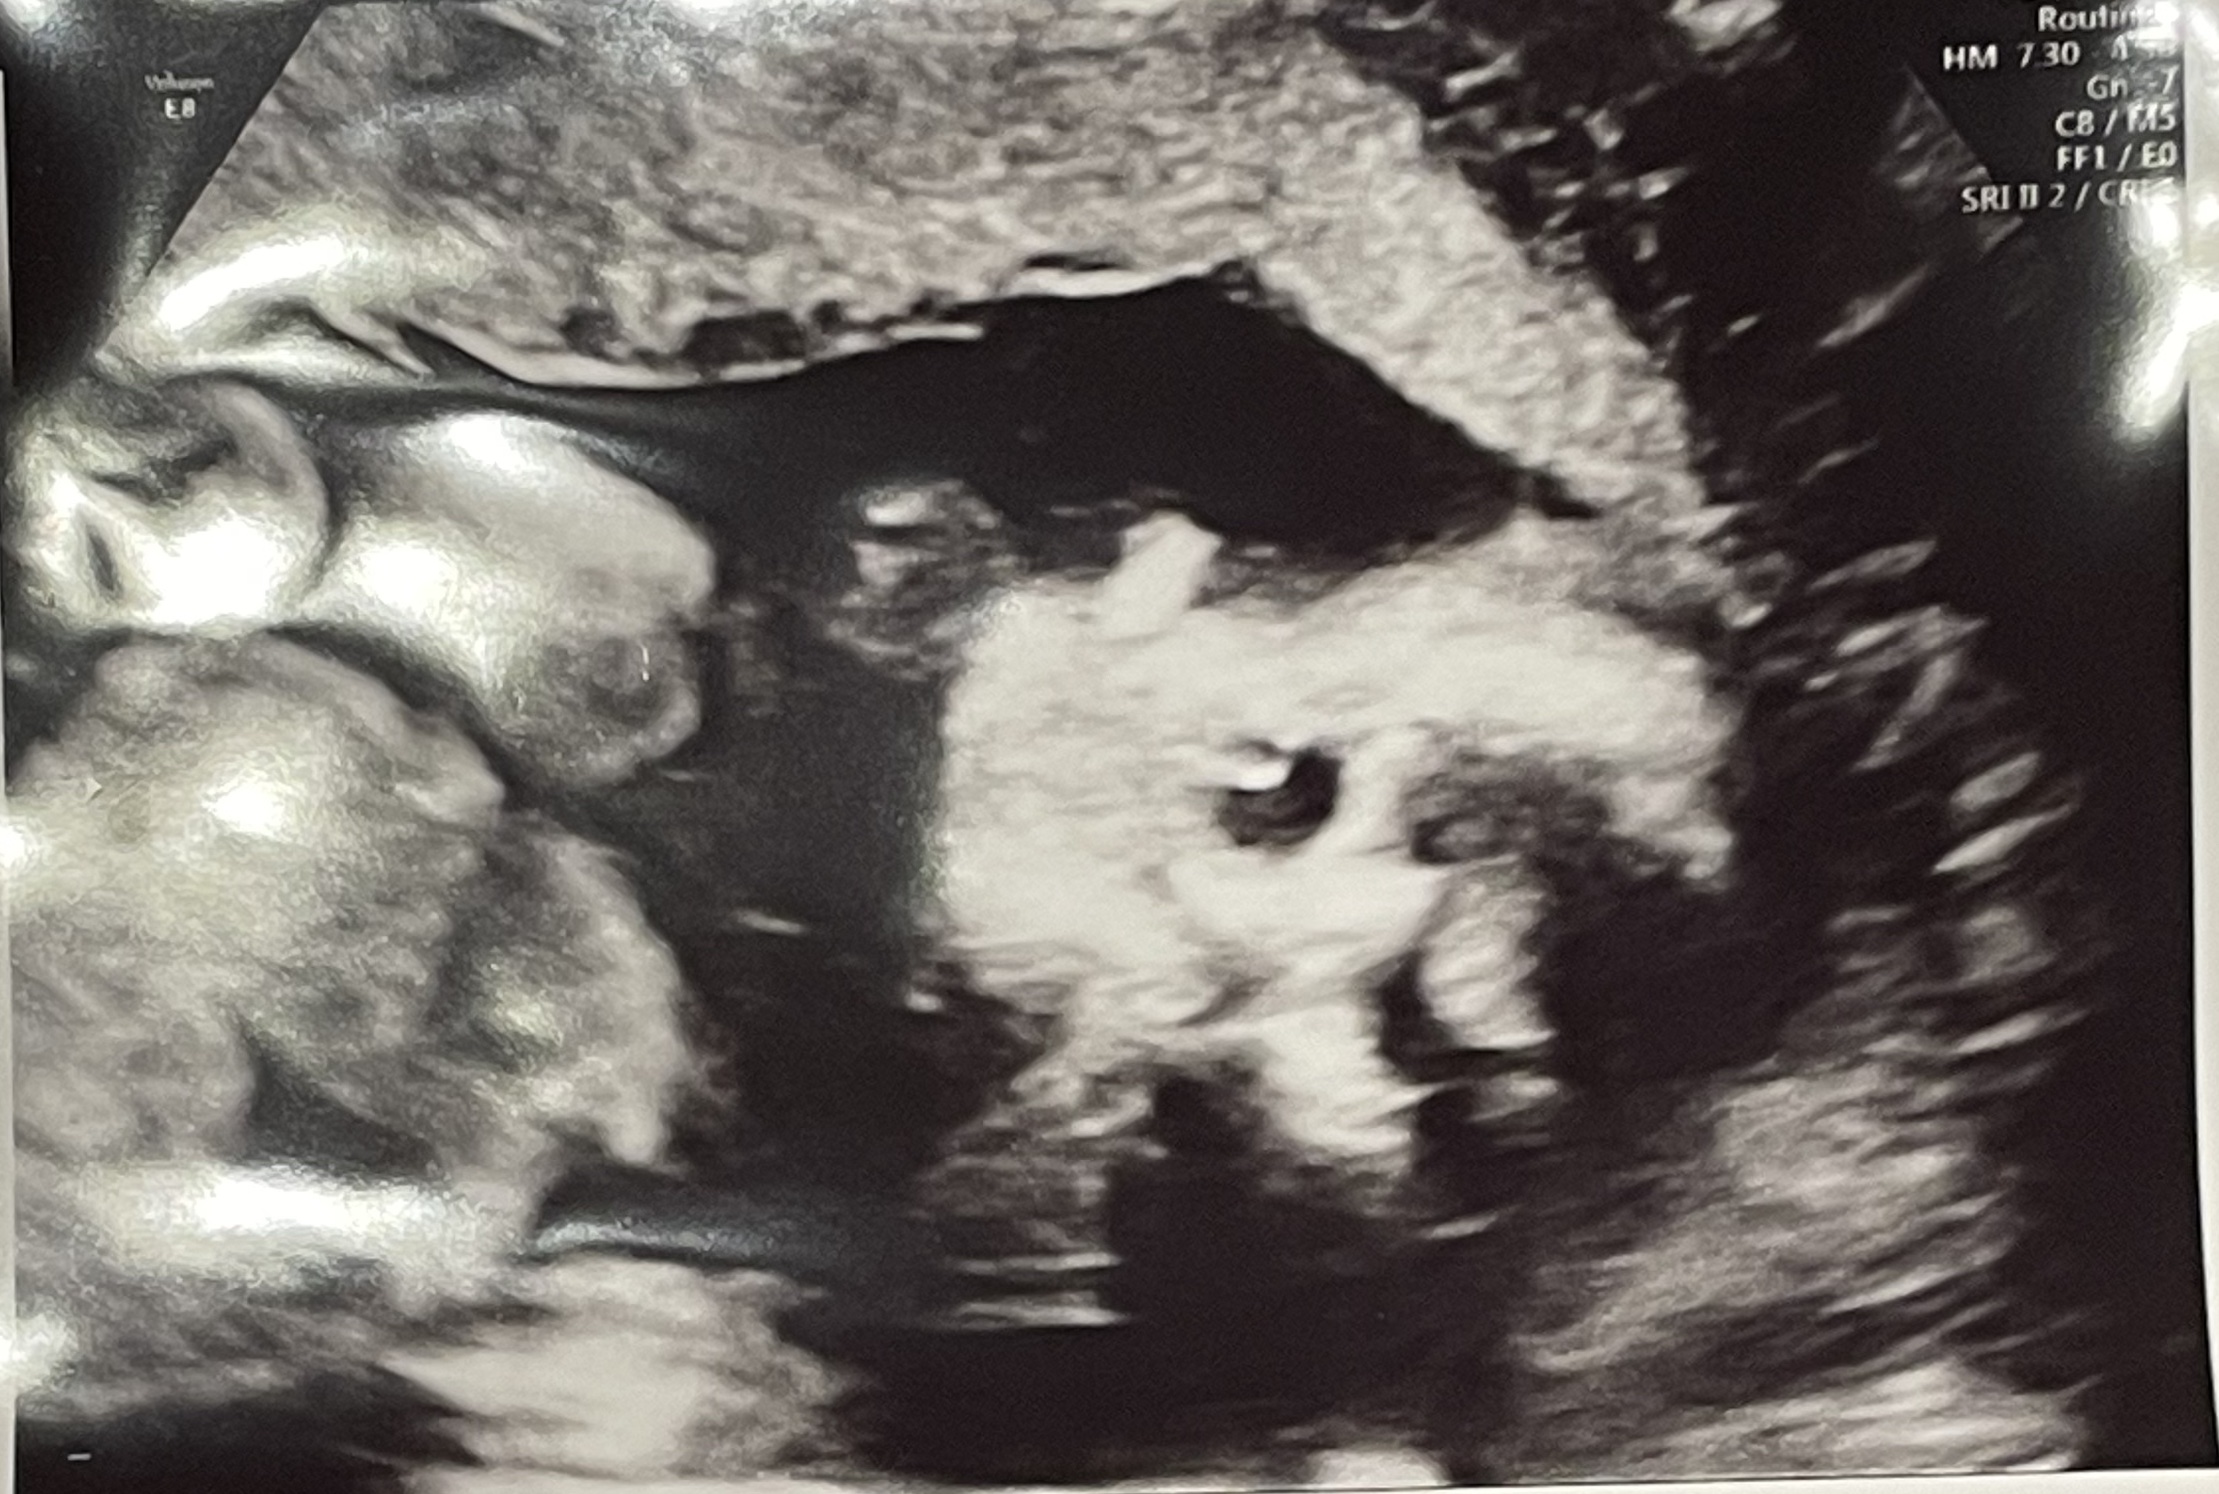

先生のエコーでの検査が一通りおわった段階で、エコーをわたしに見せながらお顔や身体のパーツを見せてくれたり、心音を聞かせてくれたりしました。

心音は聞けたのですが、赤ちゃんが元気に動いているタイミングだったので途中から音が乱れていました。

胎動とエコーでの映像とで動いていることがリンクして、本当にお腹にいるんだなぁと思った瞬間でもあります。

女の子でした!女の子はおまたの間に、「コーヒー豆」や「木の葉マーク」と呼ばれる印が目印だそうです。

女の子と言われたけど生まれたら男の子だった!というのはたまに聞く話ですが、この日は体制もよかったためか先生によると「前も下もすっきりしているので、今のところは女の子だと思っていいですよ」とのことでした。